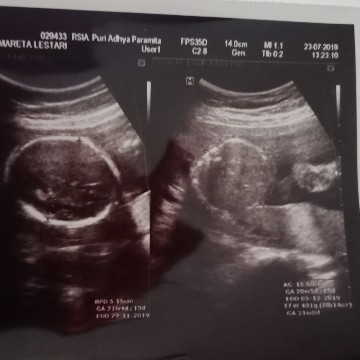

usg

Alhamdulilah td pas usg dedekny sehat . Tp kta dokter ari* ny dimulut rahim ktanya klok 2 bln lagi gk brubah posisi gk bisa lahiran normal bun. Ada yg kya sya gk bun trs hrs gmna ya

Iya klo placenta nya di bawah dan nutup jalan lahir emg gak bisa normal bun. Itu gak bisa diapa2in utu emg berkembang dgn sendirinya seiring dgn pertumbuhan janin juga..

saya juga terdeteksi plasenta rendah bunda,, usia 18w, memang jadi kepikiran sih bund, cuma saya berusaha positif.